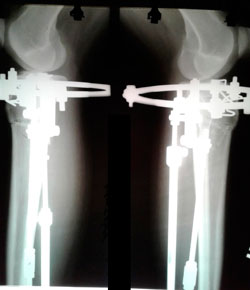

Исходник 23 года.

Дата операции - 26.08.2020

image-26-08-20-06-25-3.jpg

image-26-08-20-06-25-1.jpg